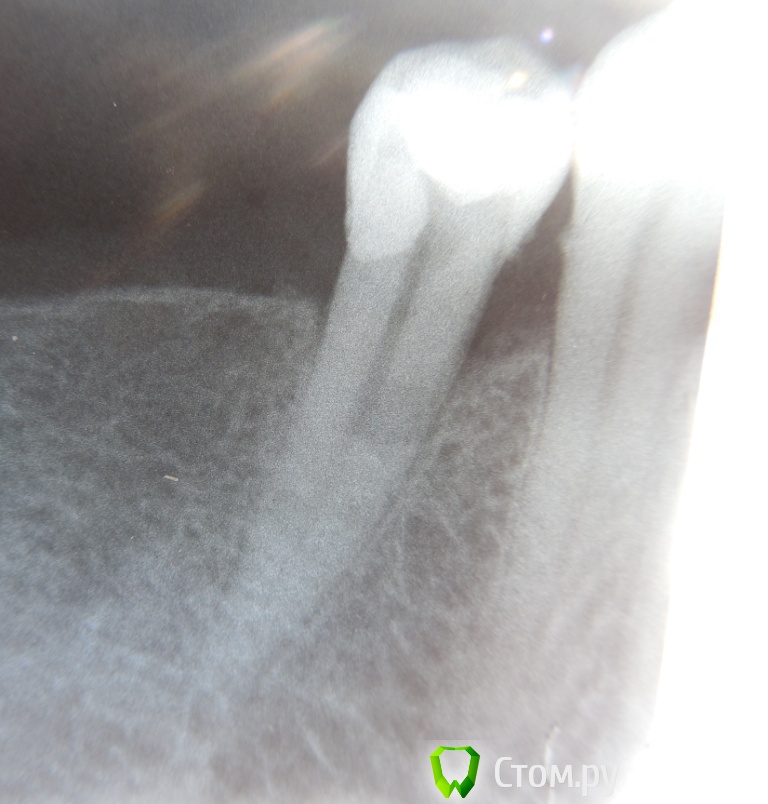

Л-Ф Опубликовано 2 апреля, 2014 Автор Поделиться Опубликовано 2 апреля, 2014 (изменено) У Вас должны быть еще снимки, после удаления нерваК сожалению,ни ДО ни ПОСЛЕ мне не делали снимки.Это я уже в платной сегодня сделала.Сейчас стоит временная,белая пломбаЭти снимки с временной пломбойДобавлю,что зуб немножко подвижный...немногоЕще вопрос.Удален ли у меня нерв полностью?И в сом низу зуба очертания какие то....может там воспаление? или мне кажется Изменено 2 апреля, 2014 пользователем Л-Ф Ссылка на комментарий

Гарриевич Опубликовано 2 апреля, 2014 Поделиться Опубликовано 2 апреля, 2014 Синяк у Вас, это гематома после укола, такое бывает... пройдет. Корневой канал еще не запдомбирован, поэтому сказать, что то о качестве не могу. Един ственный момент который сильно смущает это отсутствие снимков в процессе работы Ссылка на комментарий